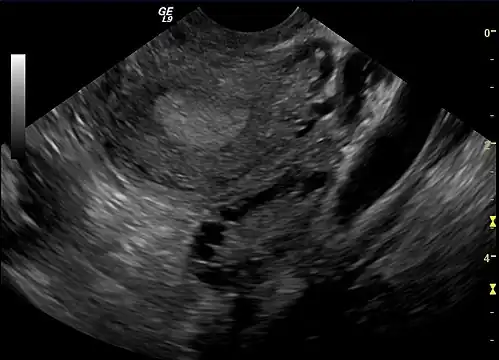

-

Polycystic ovary as seen on sonography